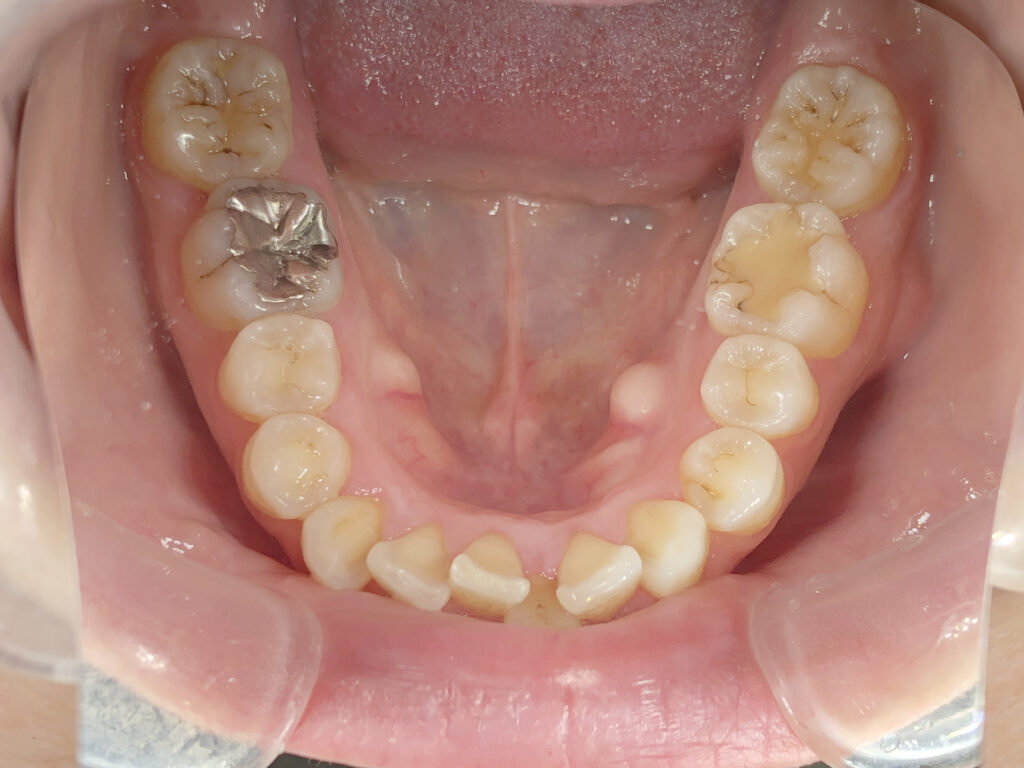

下顎

治療前

治療後